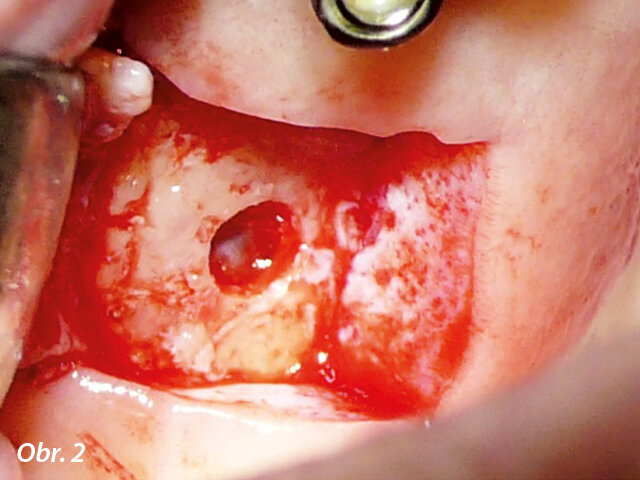

Obrázek 1 zachycuje "split-mouth" případ s oboustranným zákrokem přístrojem INTRALIFT: po oddělení malého krestálního laloku ve tvaru „knížečky“ o rozměru cca 7 × 7 mm bylo dno sinu bezpečně otevřeno pomocí ultrazvukových hrotů Piezotome (obr. 2, 3), membrána sinu oddělená vlivem hydrodynamického kavitačního účinku hrotu Piezotome TKW5 pak byla vtlačena do přístupového kanálu (obr. 4, 5), subantrální konstrukce byla vyplněna 2 cm náhodně přiřazeného biomateriálu a následně byla rána sešita.